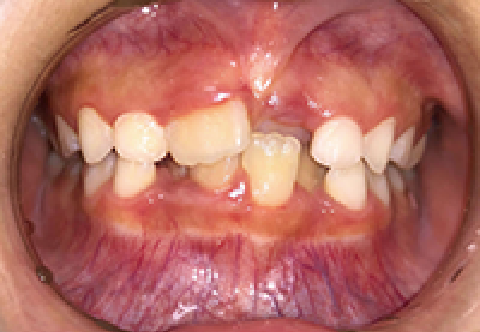

症例 : 7歳 女性

Before

After

主訴

叢生(歯がガタガタ)

治療方法

床矯正+インビザラインファースト

総額治療費

550,000円(税込)

治療期間

3年

治療のリスク・副作用

前歯を正しい位置に移動する時に、咬み合わせが不安定になることがあります。

改善ポイント

左側の前歯が反対咬合のため、床矯正だけでは改善が難しく、インビザラインファーストを併用しました。

少しずつ動かしていく必要があるため、治療期間もやや長くかかりましたが、綺麗な歯並びになりました。